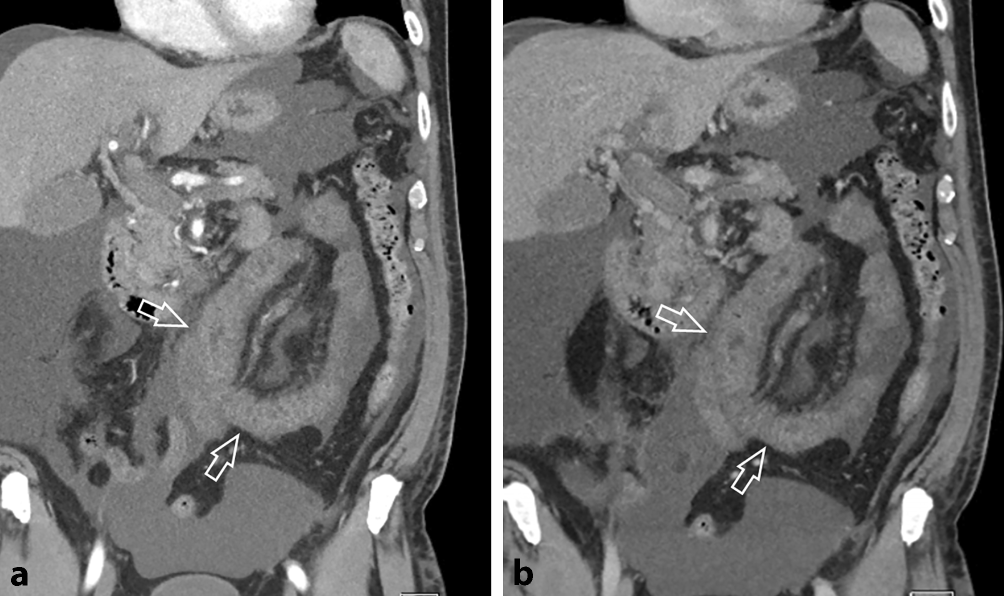

Ein 67 Jahre alter Patient mit bekannter Leberzirrhose (Child-Pugh Score A, MELD 11) wurde aufgrund seit zirka 10 Tagen bestehenden diffusen Bauchschmerzen stationär aufgenommen. Bekannt waren auch dank einer rezenten Gastroskopie das Vorliegen von Ösophagusvarizen und inzipienten Fundusvarizen. Der Patient wurde zur weiteren Abklärung zu einer kontrastmittelverstärkten Multidetektor-CT (MDCT) zugewiesen, welche eine ausgeprägte Thrombose sowohl der intra- und extrahepatischen Pfortader, der V. mesenterica superior und der V. lienalis zeigte (Abb. 1). Überdies zeigte sich aufgrund der ausgedehnten Thrombose eine Splenomegalie und auch Aszites. Aufgrund fehlender Zeichen einer Darmischämie wurde von einer chirurgischen Intervention abgesehen, es wurde stattdessen eine therapeutische Antikoagulation mit niedermolekularem Heparin und in weiterer Folge Apixaban eingeleitet. Die Abklärung hinsichtlich einer zu Grunde liegenden Gerinnungsstörung brachte kein Ergebnis, es fand sich auch keine Neoplasie. Im weiteren Verlauf kam es zum Auftreten von Melaena. In der daraufhin durchgeführten Gastroskopie fand sich kein Hinweis auf eine Blutung. Die MDCT-Verlaufskontrolle zeigte eine ausgeprägte Verdickung der proximalen Jejunumschlingen, mit Zeichen petechialer Einblutungen (Abb. 2). Die Kontrastmittel-MDCT zeigte auch eine Abgangsstenose des Truncus ceoliacus mit poststenotischer fusiformer Ektasie bei Vorliegen eines Ligamentum arcuatum. Allerdings zeigten sich keine Kollateralen zwischen Tr. coel. und A. mes. sup., was eine hämodynamisch signifikante Stenose weitgehend ausschloss. Zum Ausschluss einer paraneoplastischen Mesenterialvenenthrombose wurde nach dem Kontrastmittel-MDCT, der Gastro-Duodenoskopie und der Colonoskopie noch eine MR-Enterographie zwei Wochen später durchgeführt, welche keinen Hinweis auf einen Tumor im Dünndarm ergab, jedoch die Rückbildung des Dünndarmödems zeigte (Abb. 3). Aufgrund der bekannten und nur partiell rekanalisierten Thrombose von Pfortader, V. mes. sup. und V. lienalis zeigte sich auch eine progrediente Splenomegalie. Eine diagnostische Aszitespunktion erbrachte keine weiteren Erkenntnisse. Unter adäquater Schmerztherapie und Anpassung der internistischen Therapie konnte eine deutliche Besserung des Allgemeinzustandes erreicht werden. Die weiterführende laborchemische Abklärung der incipienten Leberzirrhose war unauffällig, sodass eine Leberbiopsie im Rahmen eines Folgeaufenthaltes geplant wurde.

Abb. 1

a Die Kontrastmittel-verstärkte MDCT zeigt eine Thrombose der intrahepatischen (Pfeil) und (b) der extrahepatischen Pfortader (Pfeil). Es finden sich auch Kontrastmittel-gefüllte Kollateralvenen ventral der Pfortader (Pfeilspitzen). c Die 3D-Rekonstruktion (Curved Planar Reconstruction) entlang der Mesenterialgefäße zeigt die ausgedehnte Thrombose der Pfortader (großer Pfeil), der V. mes. sup. und der V. lienalis (kleine Pfeile). Es findet sich auch reichlich Aszites